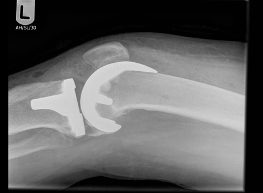

Images of Knee Replacement:

X-Ray of Knee Replacement 1